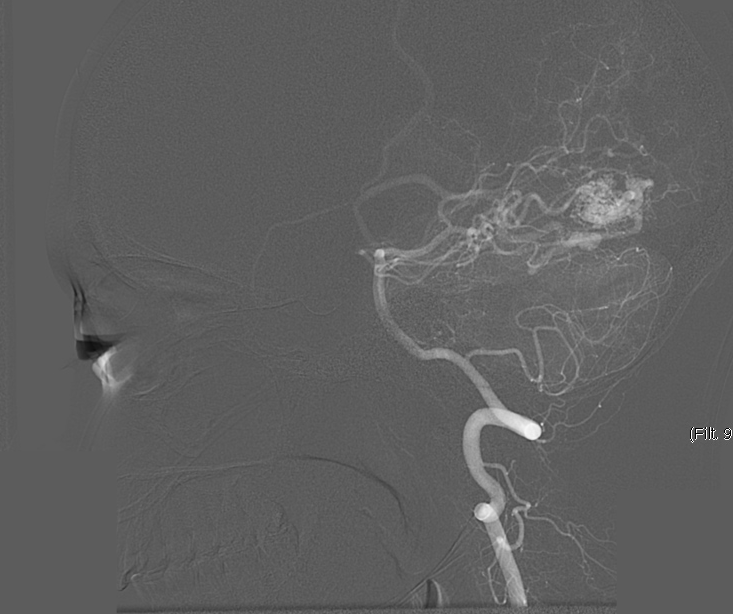

We chose FastICA to define the unmixing function and applied it on 19 DSA image series of subjects with an AVM. The series were composed of 12 to 38 images showing the malformations at different time points and were acquired at a low frame rate of 1.5fps to 6fps. As shown in Figure 2, the function was capable of decomposing the phases of vascular flow. We also generated phase-constrained color-coded overlays for DSA image series through the combination of the recovered sources and vessel masks, leading to a visualization where contrast flow appears progressively and is classified as artery, nidus and capillary, or vein. An example of this visualization is shown in Figure 3.